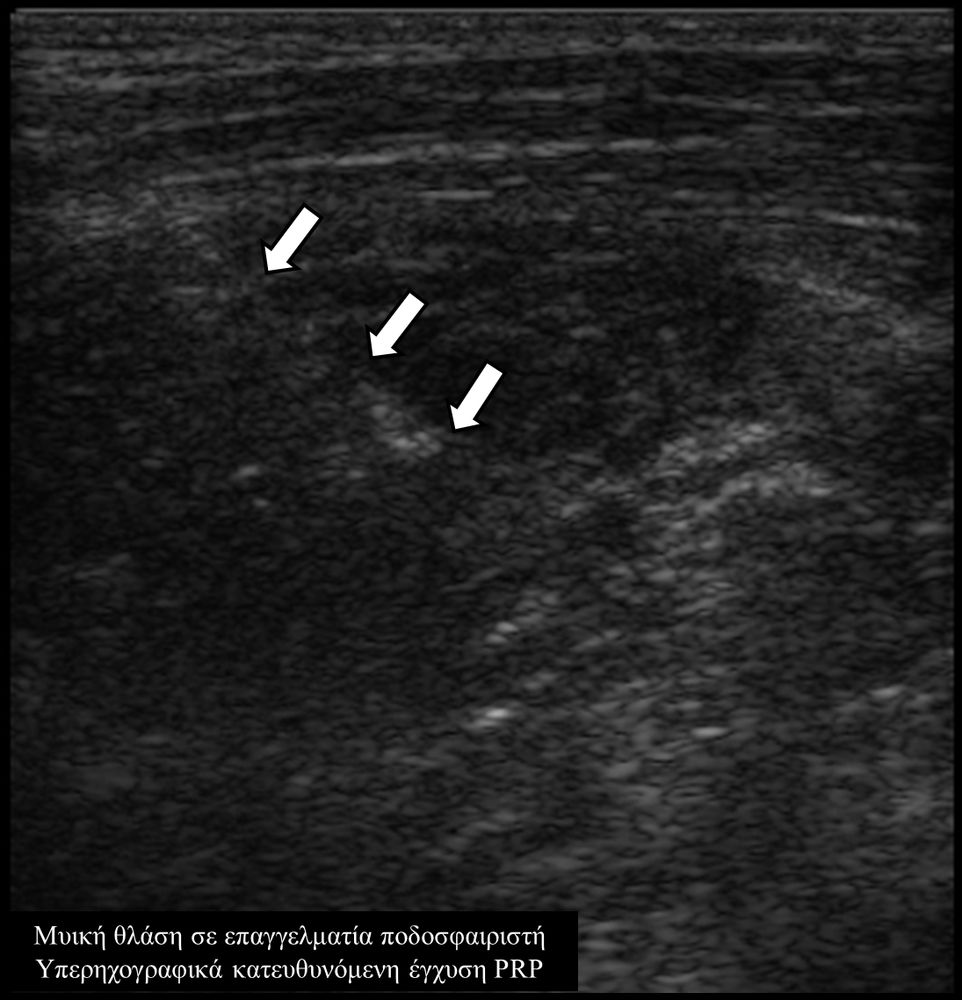

Οι κατευθυνόμενες εγχύσεις σε αθλητικές κακώσειςαποσκοπούν στη μείωση του πόνου, την ενίσχυση της αποτελεσματικότητας της φυσικοθεραπείας και την επιτάχυνση της διαδικασίας επούλωσης για την πιο γρήγορη επάνοδο του αθλητή στις αθλητικές του δραστηριότητες. Η πιο διαδεδομένη έγχυση αποτελεί η έγχυση PRP.Ανήκει σε μια σύγχρονη θεραπευτική μέθοδο γνωστή ως Ορθοβιολογική θεραπεία και βασίζεται την ικανότητα του οργανισμού να θεραπεύεται με τα δικά του αποκλειστικά θεραπευτικά μέσα χωρίς να υπάρξει χρήση φαρμάκων.Το PRP (Platelet Rich Plasma)-πλάσμα πλούσιο σε αιμοπετάλια- σήμερα αποτελεί μια θεραπευτική μέθοδο πρώτης γραμμής με σχετικά μεγάλη επιτυχία για την επούλωση τραυματισμένων τενόντων, μυών και εκφυλιστικών παθησεων όπως οστεοαρθρίτιδα.Η εφαρμογή του περιλαμβάνει μία ευρεία ποικιλία από παθήσεις όπως:

- Μυικές θλάσεις (οξείες και χρόνιες)

Η έγχυση γίνεται πάντοτε με την βοήθεια υπερηχογραφικού ελέγχου ώστε να είμαστε απόλυτα σίγουροι για το σημείο έγχυσης τοπικά.